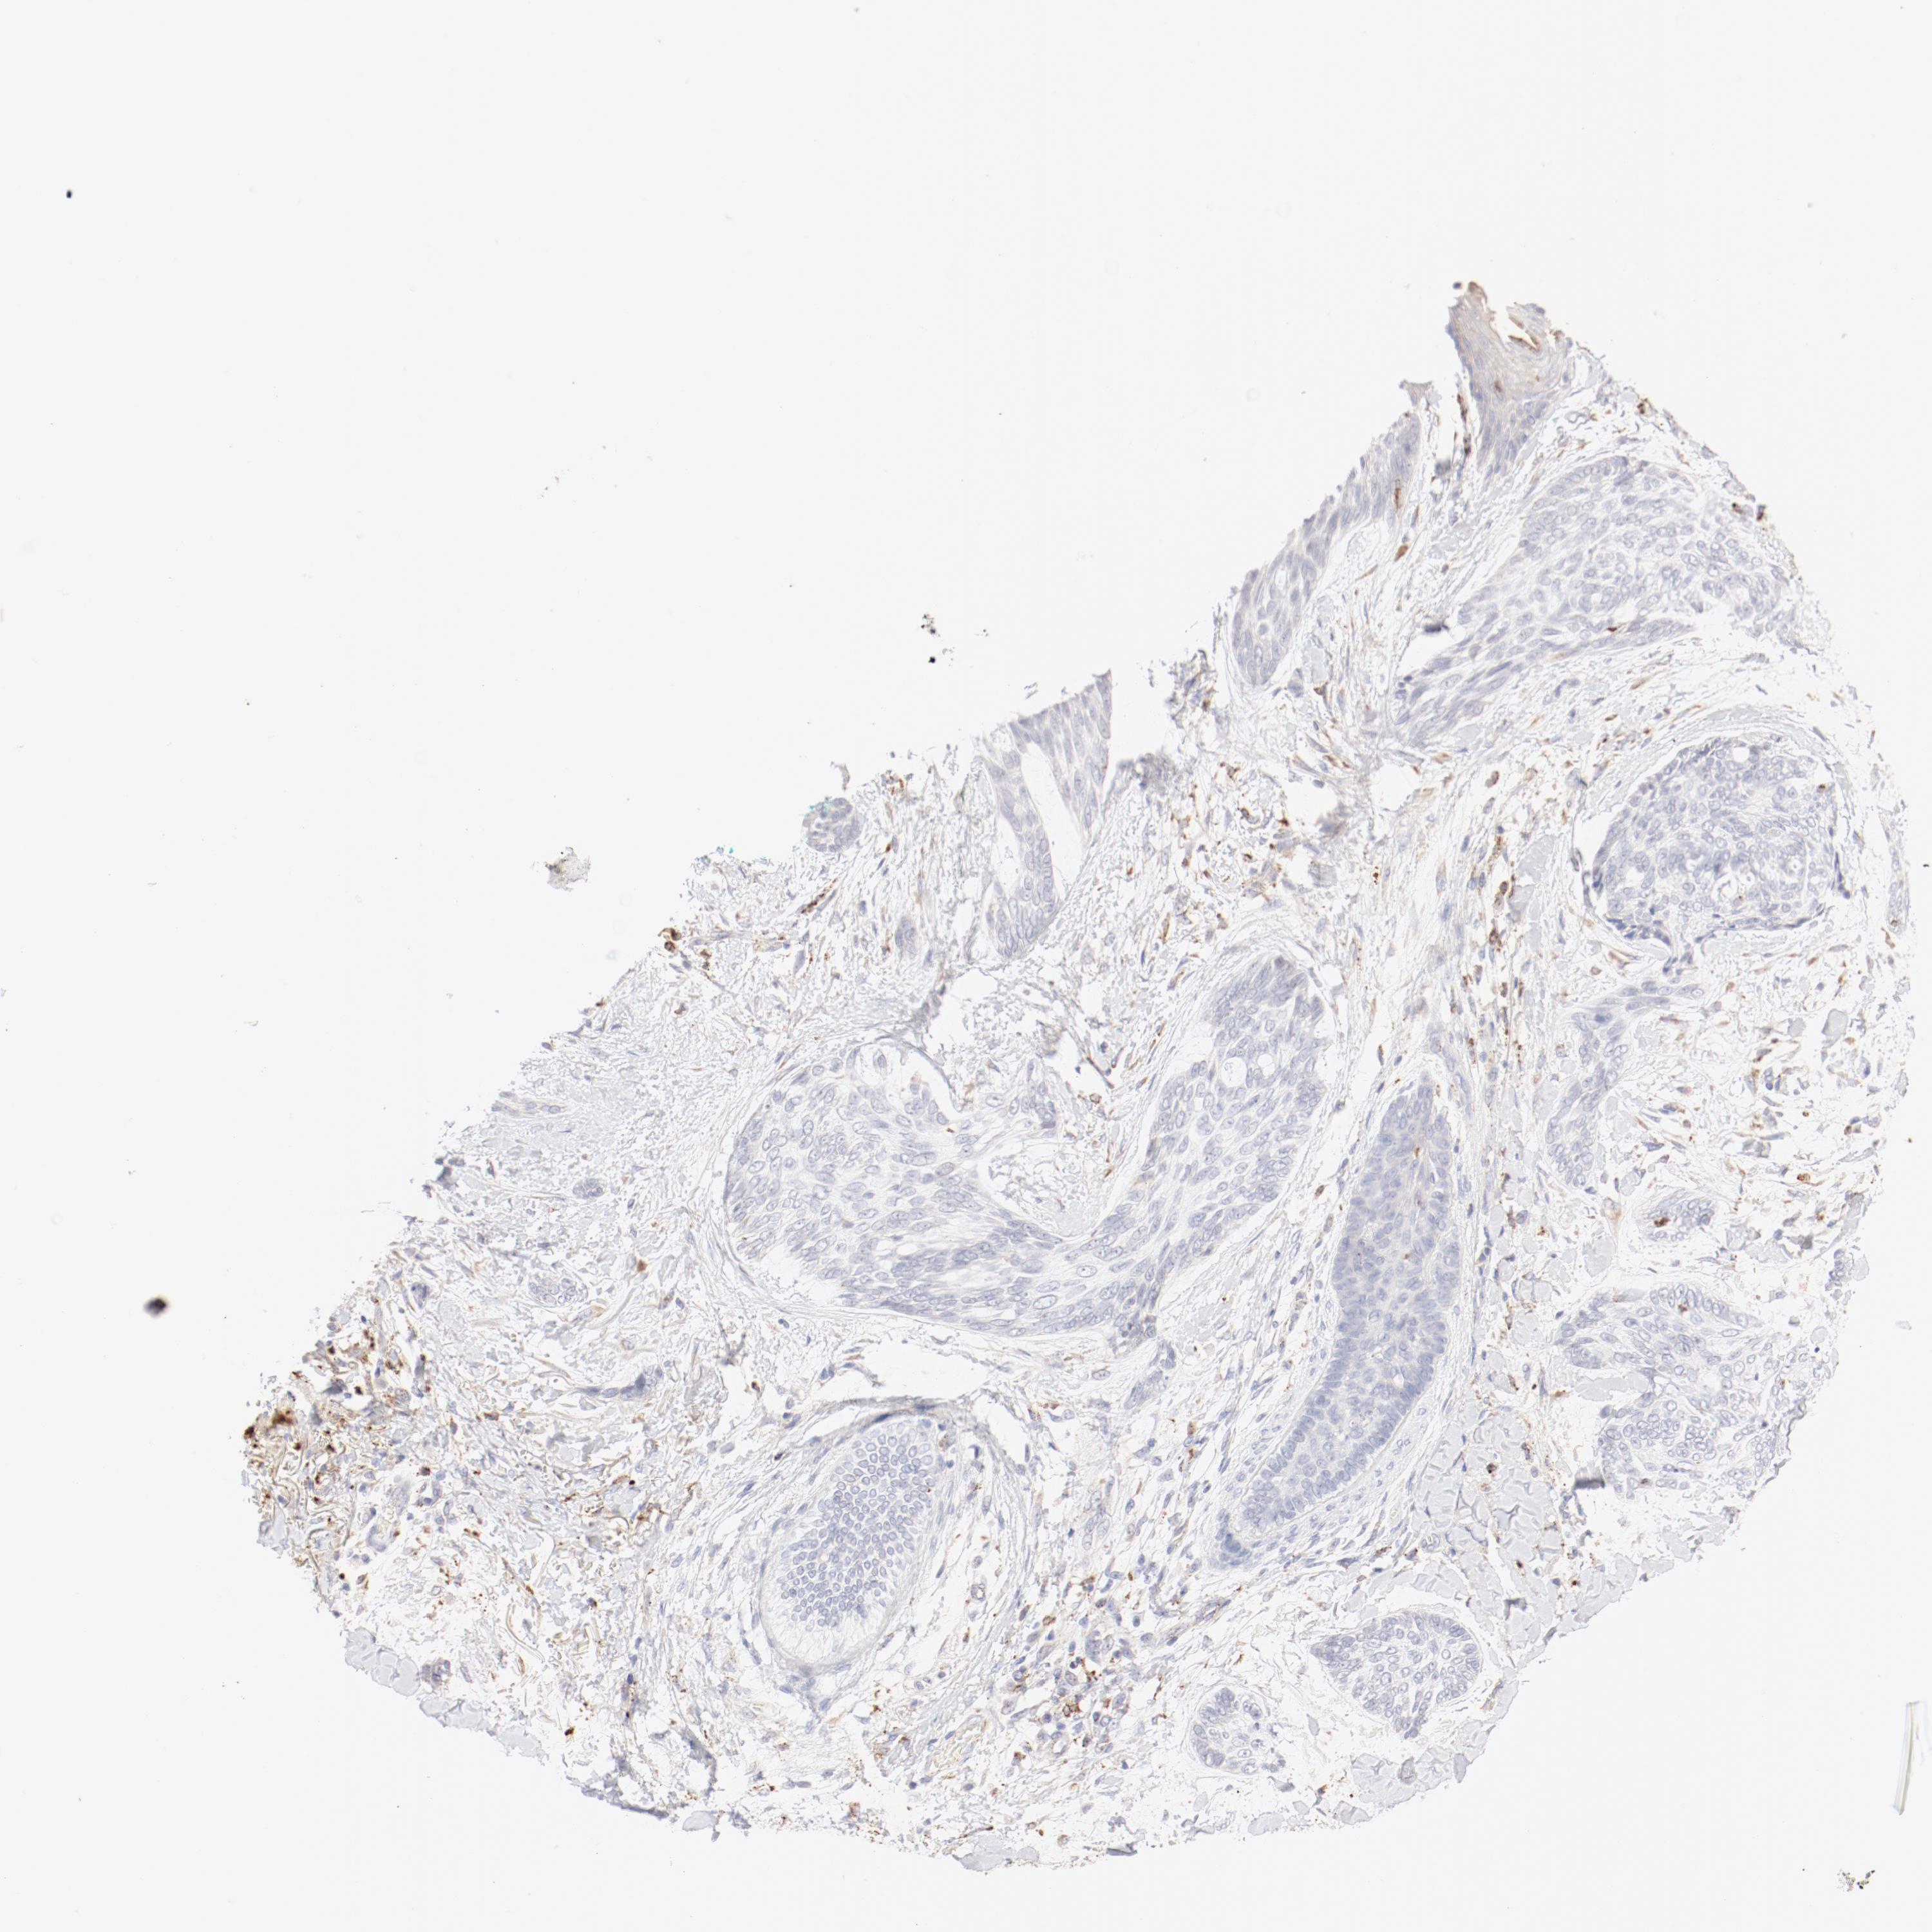

Basal cell and squamous cell cancer

SKIN CANCER - Protein expressioni

A mouse-over function shows sample information and annotation data. Click on an image to view it in a full screen mode. Samples can be filtered based on level of antibody staining by selecting one or several of the following categories: high, medium, low and not detected. The assay and annotation is described here.

Antibody stainingi

Antibody staining in the annotated cell types in the current human tissue is reported as not detected, low, medium, or high, based on conventional immunohistochemistry profiling in selected tissues. This score is based on the combination of the staining intensity and fraction of stained cells.

Each image is clickable and will lead to virtual microscopy that enables deeper exploration of all samples and also displays staining intensity scores, fraction scores and subcellular localization as well as patient and tissue information for each sample.

Antibody HPA003524

Staining

High

Intensity

Strong

Quantity

>75%

Location

Nuclear

Squamous cell carcinoma, NOS